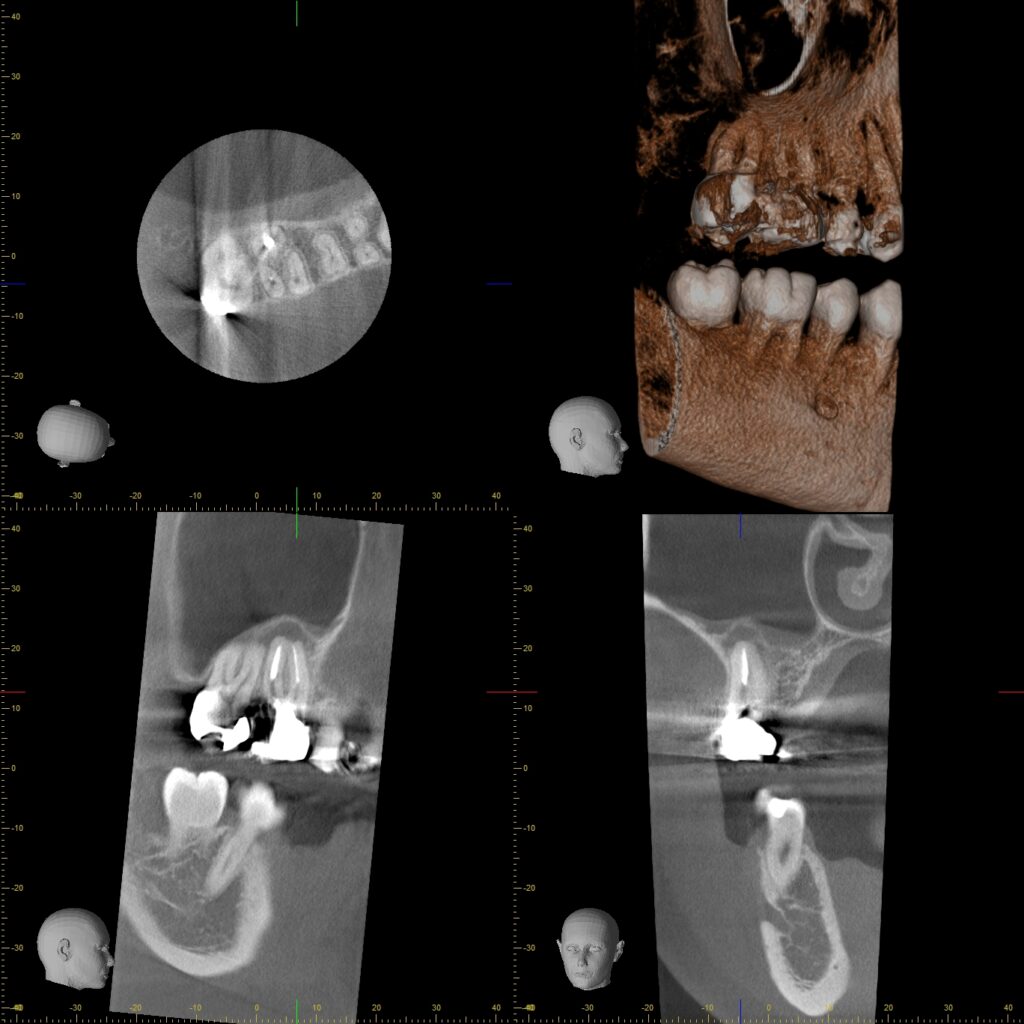

歯科用CT

根管の形状は、患者様によって、治療する歯によって大きく異なります。根管が三つ股や四つ股に分かれているものや細く奥まで伸びているもの、根管が途中で別の根管と結合しているものなど、その形状は千差万別です。 根管治療を成功させるためには、この複雑な根管の形状を正確に把握し、汚染された神経や血管、歯質を残すことなく除去しなければなりません。当院では、歯科用CTを導入し、治療対象の歯をあらゆる角度から分析して正確な治療を可能にしています。